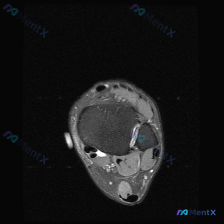

看到一个挺有代表性的读片疑问,整理了完整分析思路分享给大家。 病例基础信息 这是一张踝关节上方轴位T2序列MRI,用户的疑问是:图像中是否能观察到软组织积液? 影像基础评估结果 先给大家整理这份影像的客观发现: 1. 骨骼结构:胫骨、腓骨远端骨皮质连续,骨髓信号正常,下胫腓联合韧带清晰,没有信号增高...